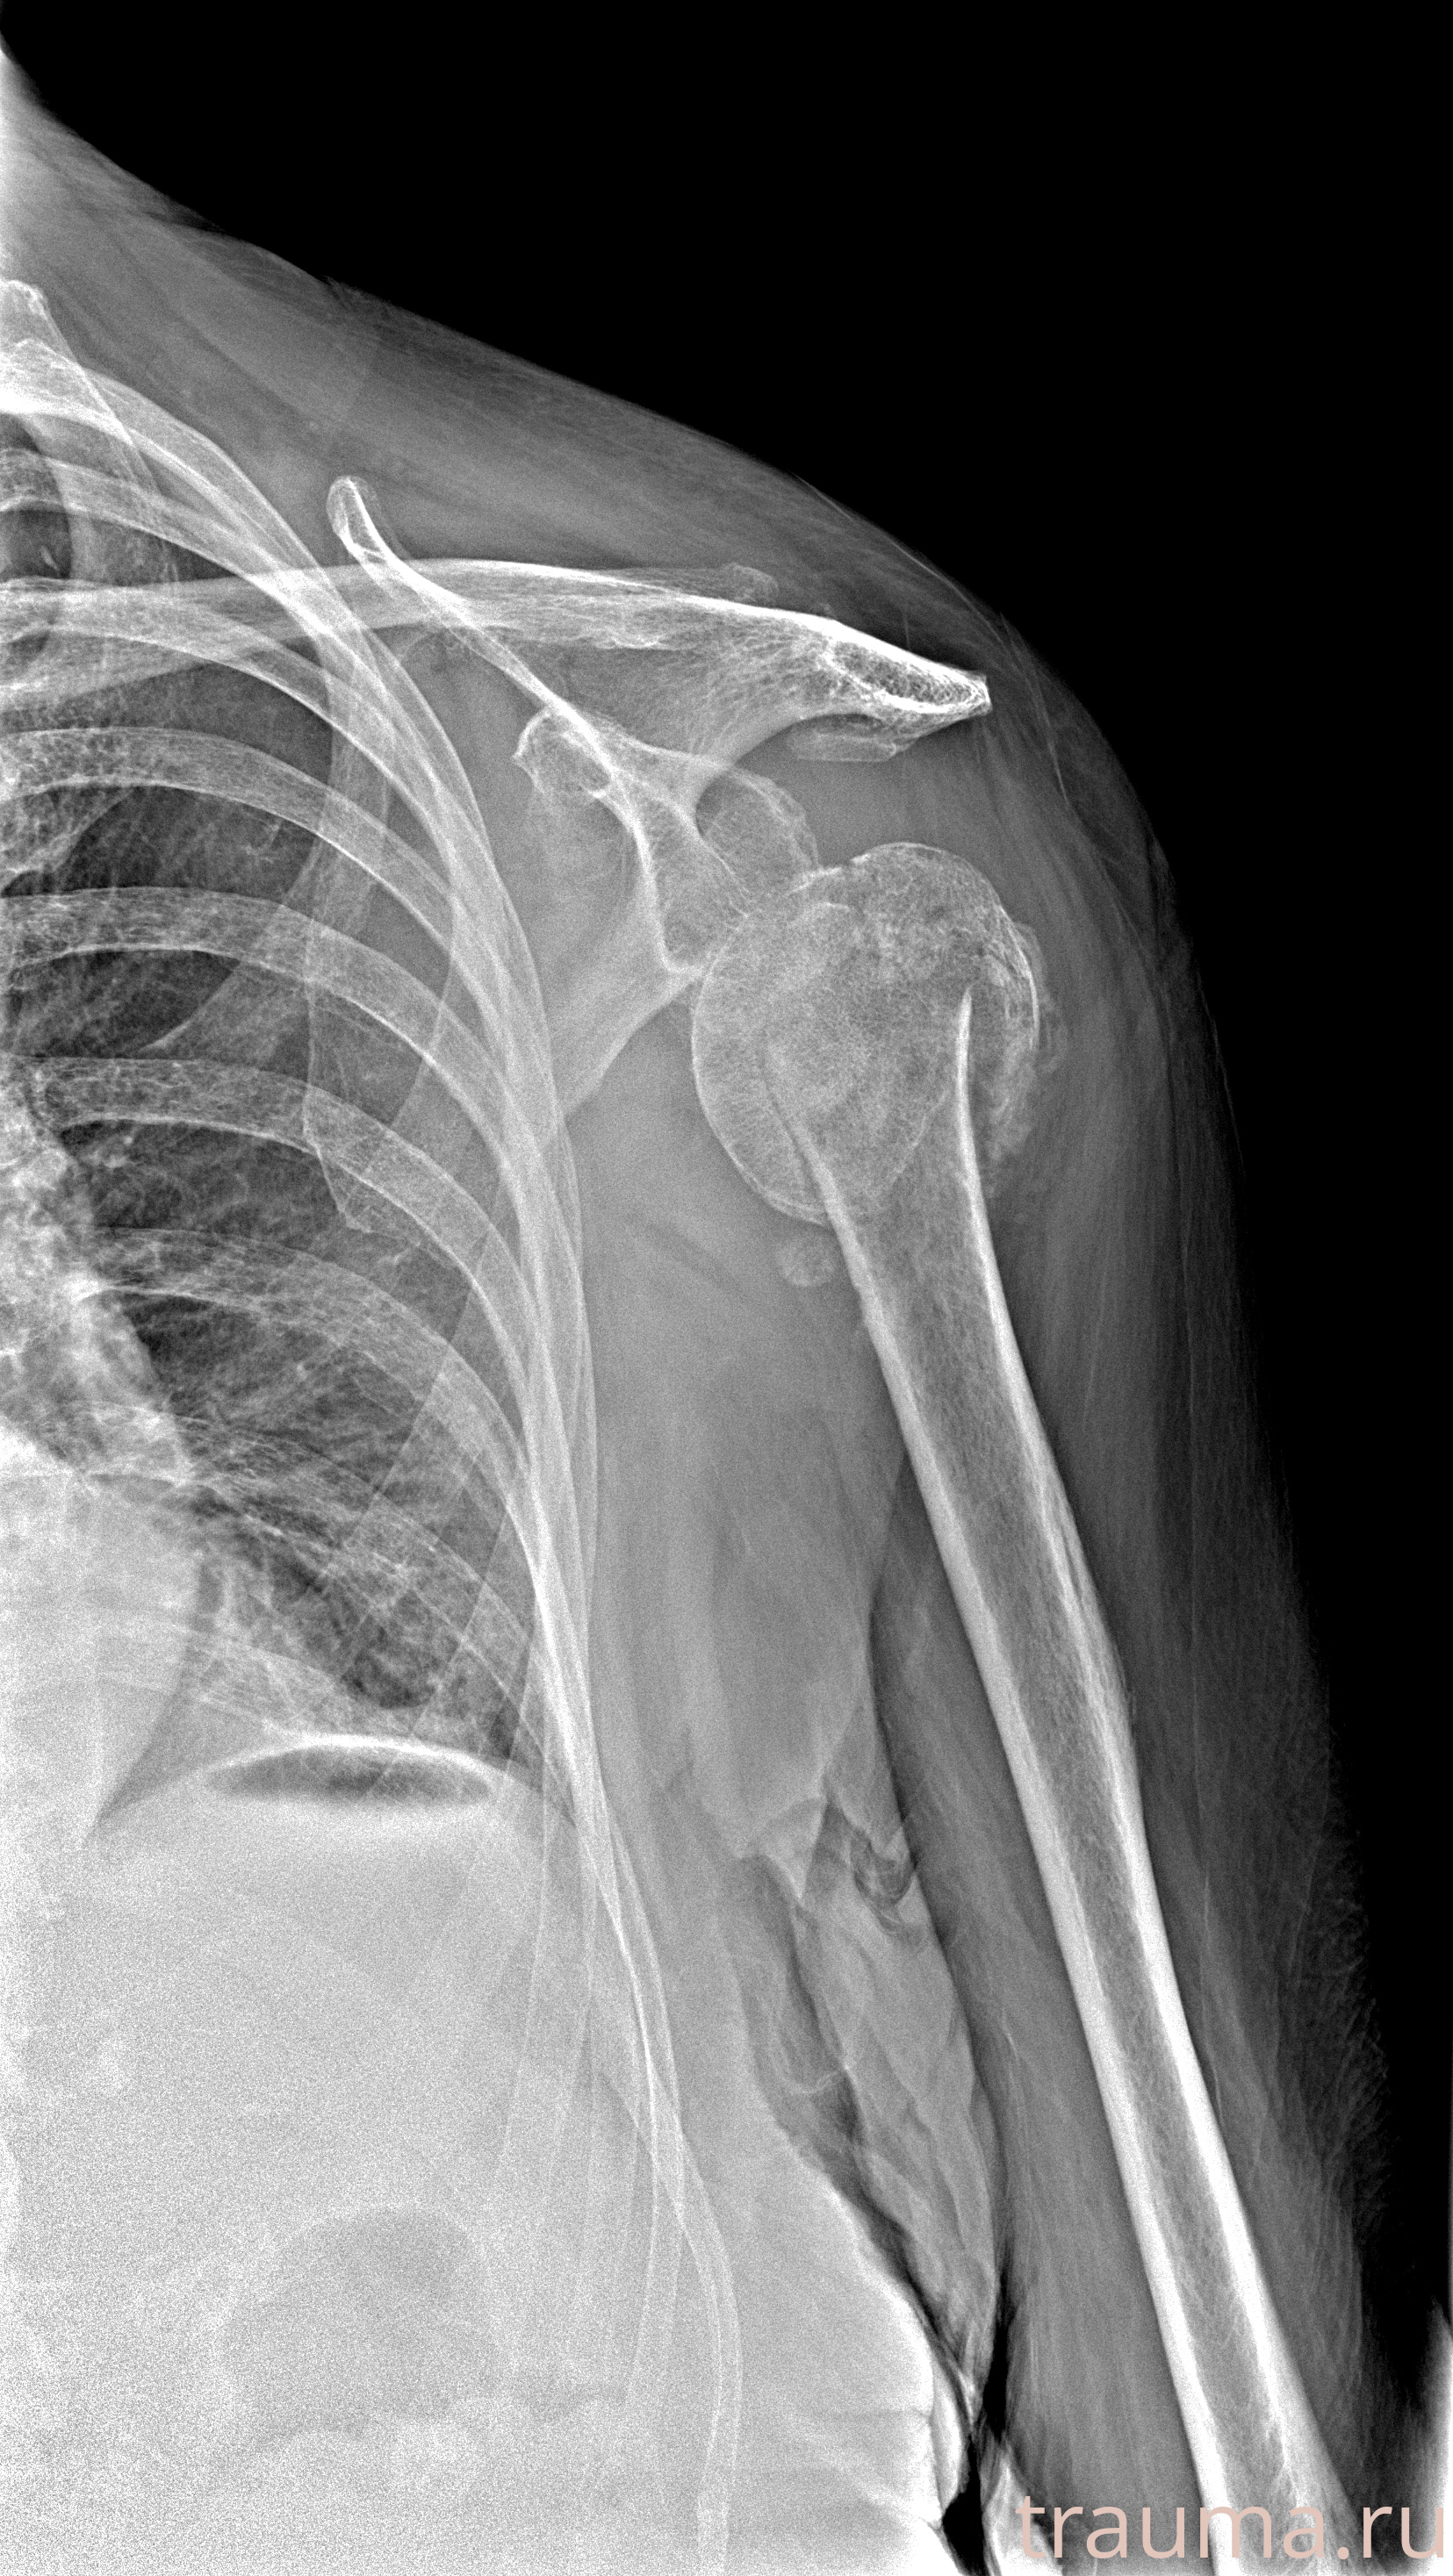

Рентген на дому: по вашему адресу приезжает врач-рентгенолог, травматолог-ортопед с мобильным рентгеновским аппаратом, проводит диагностику травмы или заболевания, делает необходимые рентгенограммы, дает рекомендации по дальнейшему лечению. Получить качественные снимки в домашних условиях возможно благодаря уникальной методике, разработанной МосРентген Центром для института  Склифосовского